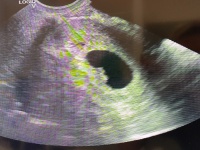

Tegnap megvolt az első vizsgálatom. 10,7 mm jó szívműködéssel, szóval eddig minden szuper! ![]()